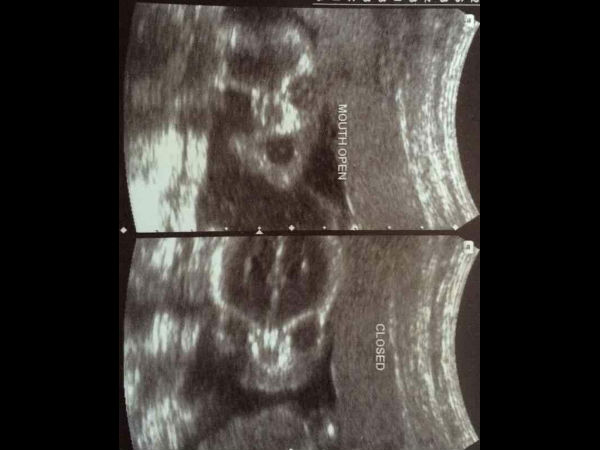

చిత్రం #4 భంగిమ!

ఈ బిడ్డ ఖచ్చితంగా గర్భంలో అన్నీ నేర్చుకుని, పుట్టుక భంగిమలో ఉంటాడు! ఈ రెండు రకాల అల్ట్రాసౌండ్ స్కాన్ లను పరిశీలించండి, ఒక స్కాన్ లో నోరుతెరుచుకుని అసహజంగా ఉంటాడు, రెండవ స్కాన్ లో నోరు మూసేసి ఉంటాడు! తను బైటికి రాబోతున్నాడు అన్న విషయం అతనికి తెలుసు, మేము పందెం కాస్తాము!